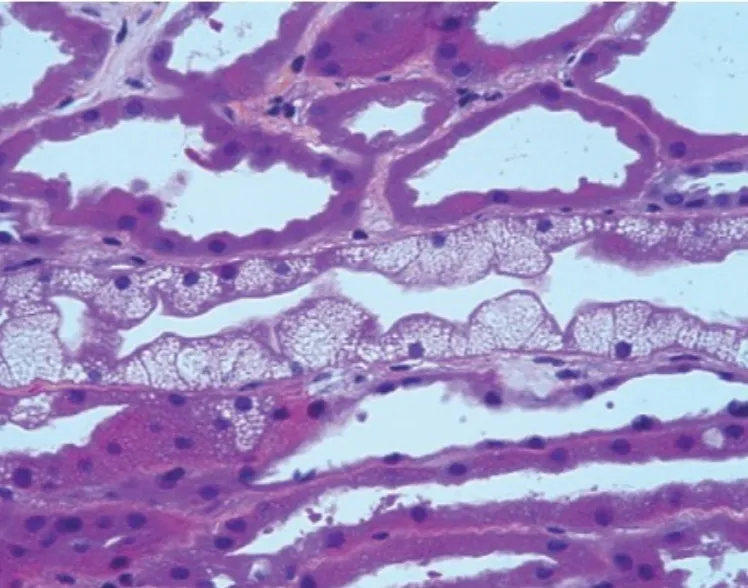

Este vídeo apresenta, de forma didática e baseada em evidências, os principais achados da tese de doutorado sobre amiloidose renal, com foco em proteômica glomerular e ativação do complemento. São discutidos aspectos diagnósticos, implicações fisiopatológicas e correlações clínico-patológicas relevantes para a prática do nefrologista. O conteúdo sintetiza dados inéditos de matriz extracelular glomerular e diferencia perfis entre subtipos de amiloidose. Trata-se de um material aprofundado e acessível, ideal para atualização de especialistas na área.